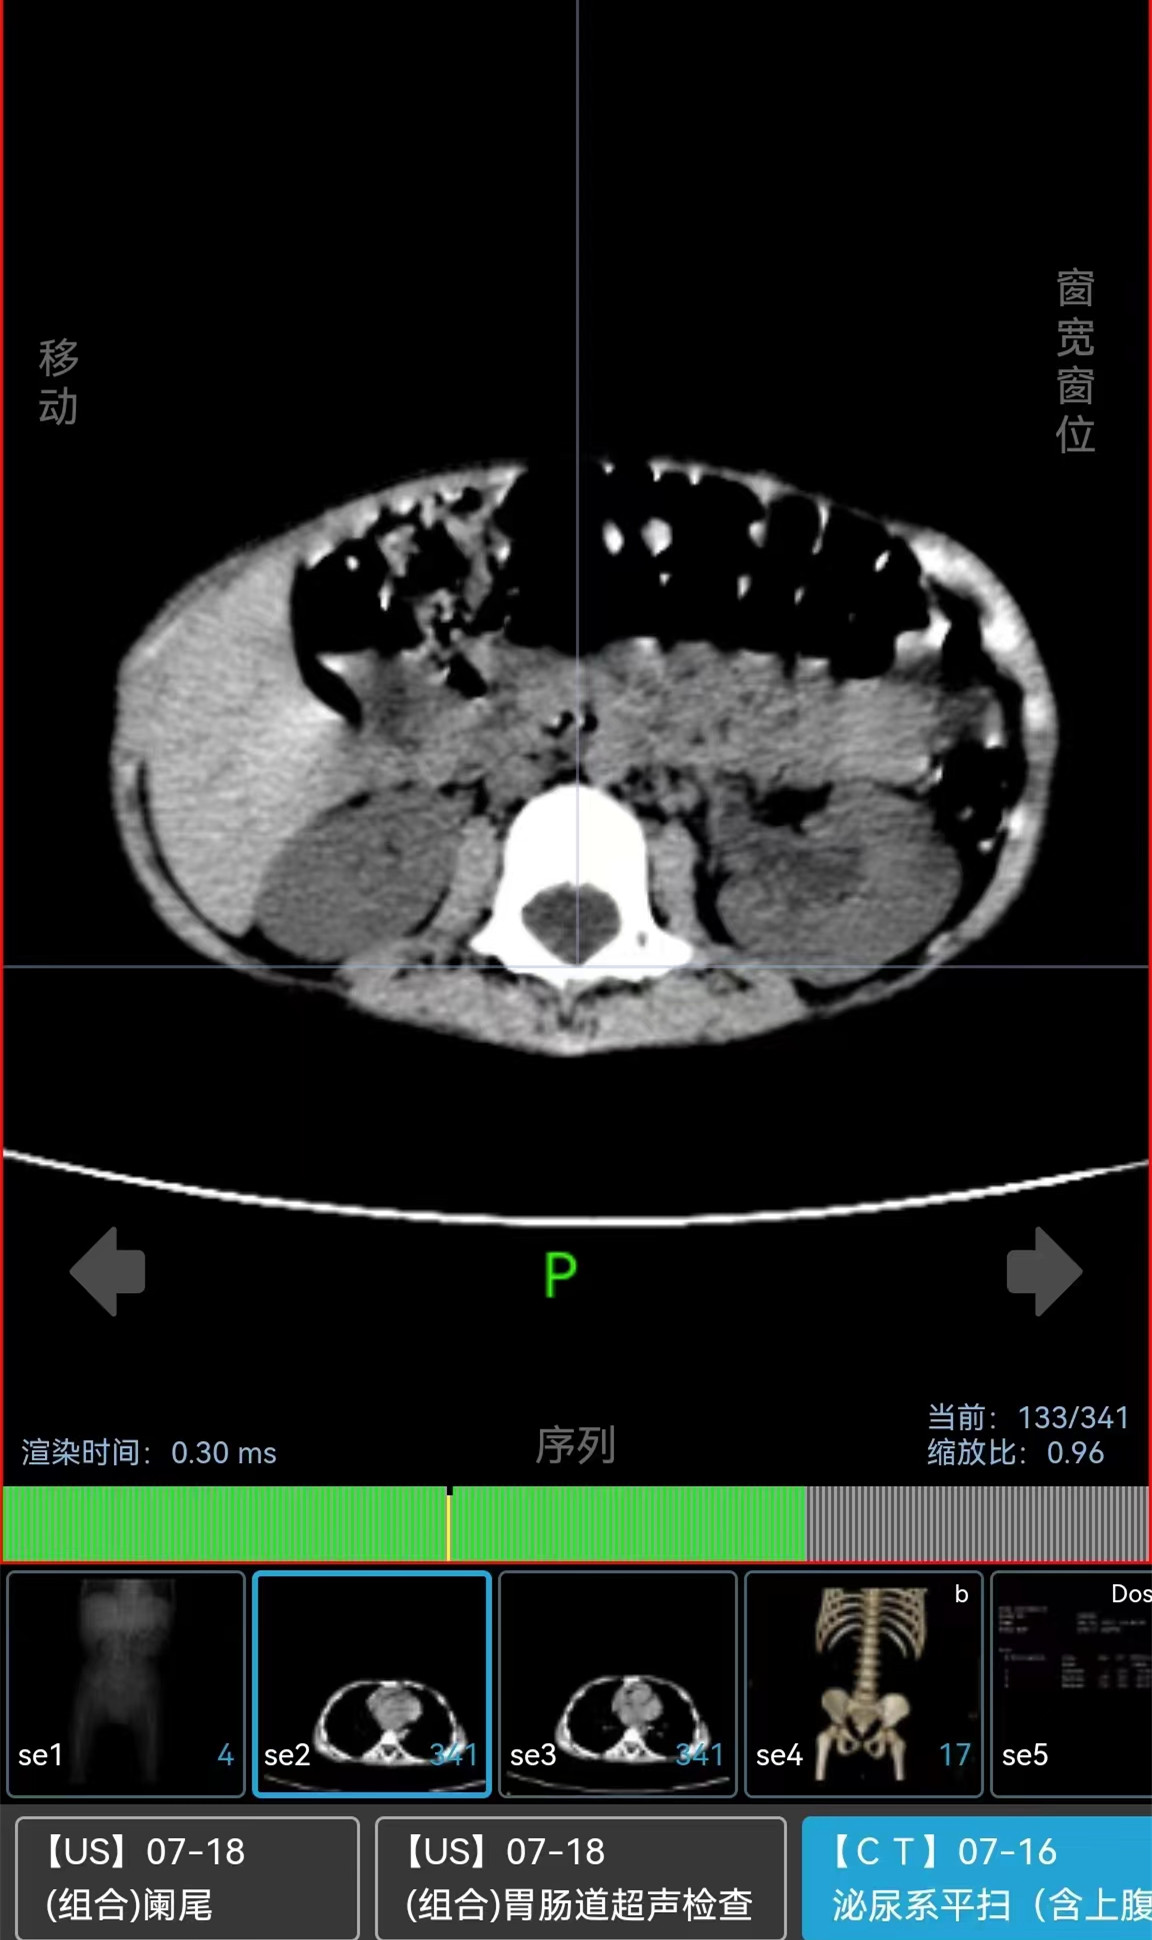

▲术前CT图片显示左肾多发结石,同时伴有左肾积水并感染。